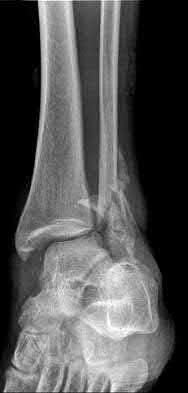

4. # After undergoing the treatment seen in Figure A, when should a patient be expected to safely operate the brakes of an automobile?

Corrent answer: 4

Figure A shows a patient after an open reduction and internal fixation of a bimalleolar ankle fracture.

Egol et al showed that by nine weeks, the total braking time of patients who had undergone fixation of a displaced right ankle fracture returns to the normal, baseline value.

Egol et al, also found that appropriate braking time returns at a point 6 weeks after initiation of weightbearing after treatment of lower extremity long bone and periarticular fractures, as examined with a driving simulator. No differences were seen in return of braking time between periarticular fractures and long bone injuries.